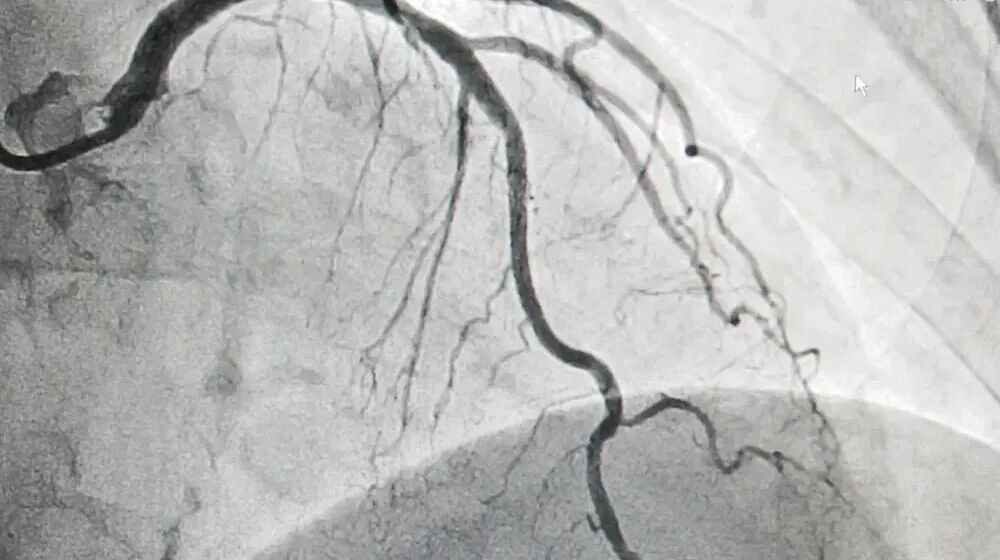

冠脉造影

检查时,将导管经股动脉或桡动脉插入冠状动脉,注入造影剂后X光成像,直接显示血管内腔狭窄程度。

适用范围

确诊冠心病、评估血管狭窄程度,是制定心脏手术方案的关键依据。

优劣势分析

优势:结果准确、可即时干预;图像分辨率高,能清晰显示微小斑块。

劣势:有创操作,需住院,存在出血、感染或血管损伤风险;费用高。